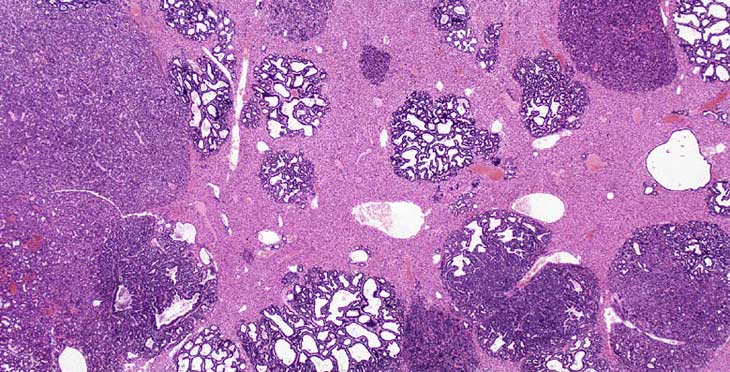

By 4-weeks of age much of the liver is replaced by areas of ductular formation, cholangial neoplasms, and hepatocellular neoplasms in AL-TAg x AL-myc mice.